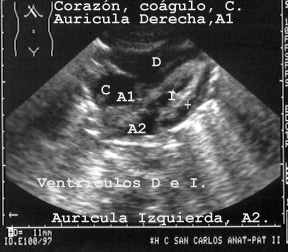

El corazón se mira desde zonas paraesternales (Fig 55)

o a través del hígado como ventana. (Fig 56).

Se ven los ventrículos, septo, válvulas y aurículas. El relieve que hay en el techo de la aurícula derecha de la Fig 56, corresponde a un coagulo postmortem.